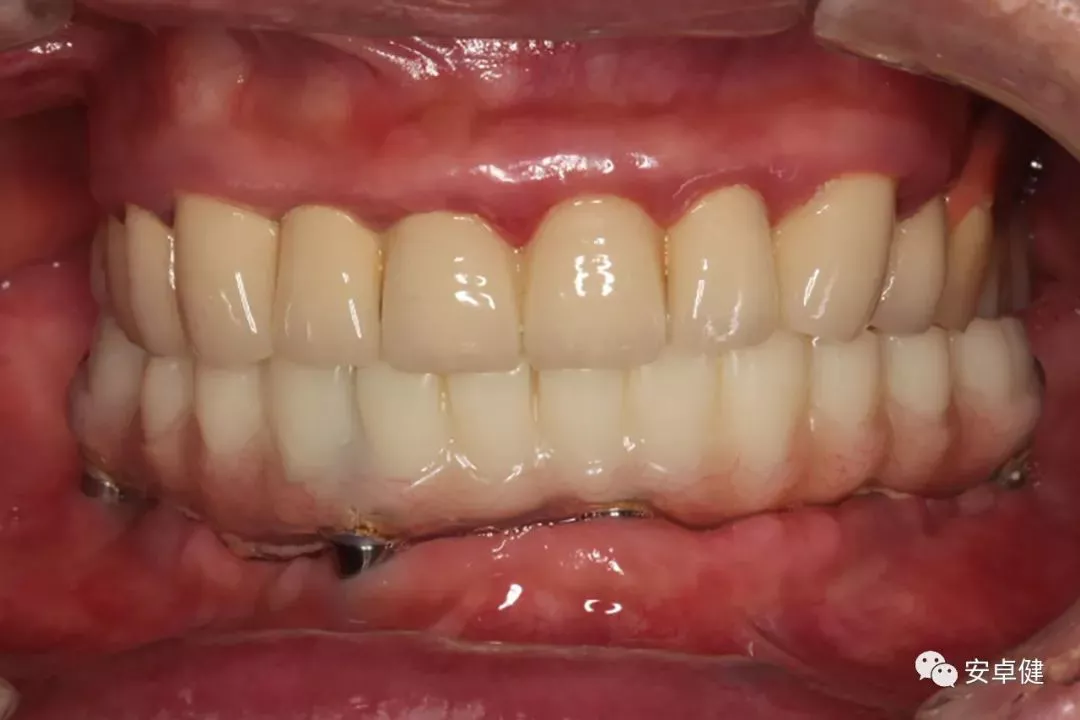

最终修复后8个月

戴牙后8个月复诊正面咬合照

戴牙后8个月复诊正面微张照

戴牙后8个月复诊合面照

• 随访可见患者口腔卫生状况可,牙龈无红肿;

• 下颌修复体状态良好,无修复体机械并发症;

• 种植体基台稳定性良好,无松动;

• 种植体无松动,周围无红肿、溢脓及疼痛表现;

• 正中、前伸及侧方咬合检查可见咬合印记分布均匀,咬合关系良好;

• 患者反映日常使用良好,舒适性佳,满意度高。

完成最终修复体及其后8个月的随访,可见种植体周牙槽骨稳定,口内种植体周围软组织无明显炎症,在美观和功能方面都取得了较为满意的结果。该病例获得了较为稳定的临床效果,可为无牙颌患者的临床诊疗工作提供一定的参考。故临床中针对符合种植适应证的无牙颌患者,可结合患者综合情况,考虑为其制定个性化全口固定式种植义齿的修复方案。